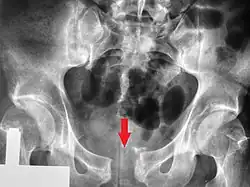

A pelvic X-ray showing an open book fracture

Open book fracture

One specific kind of pelvic fracture is known as an 'open book' fracture. This is often the result of a heavy impact to the groin (pubis), a common motorcycling accident injury. In this kind of injury, the left and right halves of the pelvis are separated at front and rear, the front opening more than the rear, i.e. like an open book that falls to the ground and splits in the middle. Depending on the severity, this may require surgical reconstruction before rehabilitation.[12] Forces from an anterior or posterior direction, like head-on car accidents, usually cause external rotation of the hemipelvis, an “open-book” injury. Open fractures have an increased risk of infection and hemorrhaging from vessel injury, leading to higher mortality.[13]